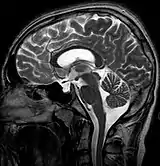

MRI of Empty Sella

Empty sella syndrome is the condition when the pituitary gland shrinks or becomes flattened, filling the sella turcica with cerebrospinal fluid instead of the normal pituitary.[2] It can be discovered as part of the diagnostic workup of pituitary disorders, or as an incidental finding when imaging the brain.[1]

Empty sella in MRI

The diagnosis of empty sella syndrome, done via examination (and test), may be linked to early onset of puberty, growth hormone deficiency, or pituitary gland dysfunction (at an early age).[2] Additionally there is: